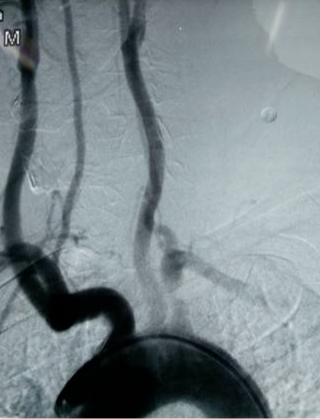

▲DSA示左側鎖骨下動脈起始段重度狹窄

術后:

▲DSA示左側鎖骨下動脈起始段支架植入術后